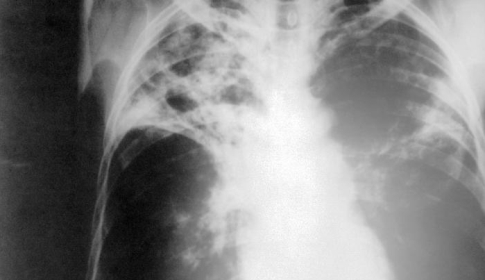

Extensively Drug Resistant Tuberculosis

CDC